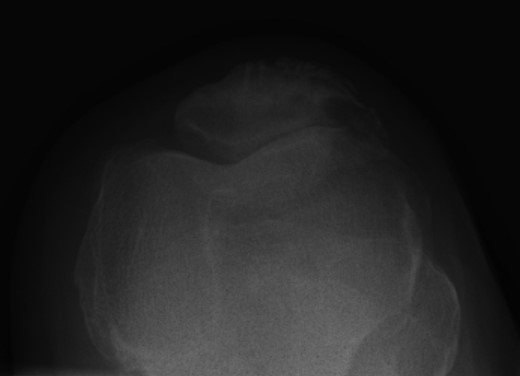

Repeat radiographs performed by his general practitioner 19 months after initial presentation (Figs 4–6) revealed a large lucency within the patella and a discontinuity in the anterior cortex of the inferior pole suggesting pathological fracture. A bone scan was arranged and demonstrated isolated abnormal tracer activity around the left patella (Fig. 7). Due to the pacemaker a computed tomography (CT) scan was performed to further characterize the lesion. This confirmed a large lucent area occupying most of the patella with multiple areas of cortical disruption along its anterior border (Fig. 8). Since the exact nature of the lesion could not be determined an ultrasound-guided biopsy was suggested but ultrasound screening revealed the lesion to be highly vascular (Fig. 9). In view of this the radiologist performed a renal ultrasound, which revealed a large mass arising from the superior pole of the left kidney. Subsequent CT of the chest, abdomen and pelvis followed demonstrating the extent of disease. There was a large (13 × 8.5 × 9 cm) mass arising from the superior pole of the left kidney (Fig. 10), the appearances of which were consistent with a primary RCC. Metastases were found in both adrenals and lungs, but no other bone metastases. Since diagnosis, the patient has had a left nephrectomy and is currently receiving radiotherapy and zolendronic acid treatment for the patella metastasis. At the time of writing this report the patient's patella lesion continues to be managed non-operatively.